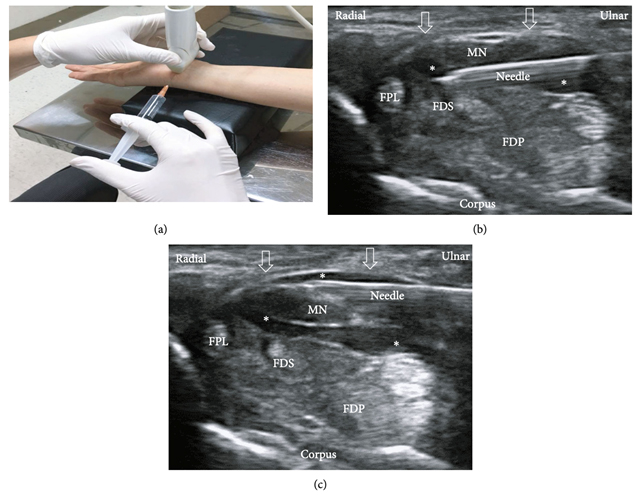

This type of injection requires precision when injecting around the nerve, so it must be performed under ultrasound guidance: Ultrasound-guided 5% DW CTS injection.